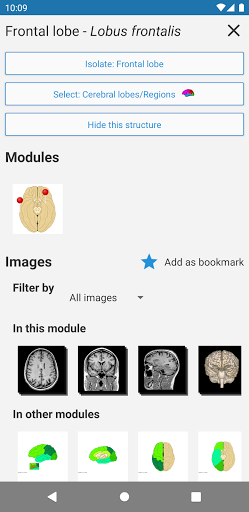

*Vista detallada mejorada de partes anatómicas para una identificación más fácil en imágenes del módulo actual y otros.

-Nueva opción para expandir galerías de imágenes en la pantalla de información de estructura anatómica.

- "Filtrar por", en la vista de detalles ahora puede filtrar las imágenes que contienen la estructura anatómica por modalidad

- "Filtrar por", en la vista de detalles ahora puede filtrar las imágenes que contienen la estructura anatómica por modalidad